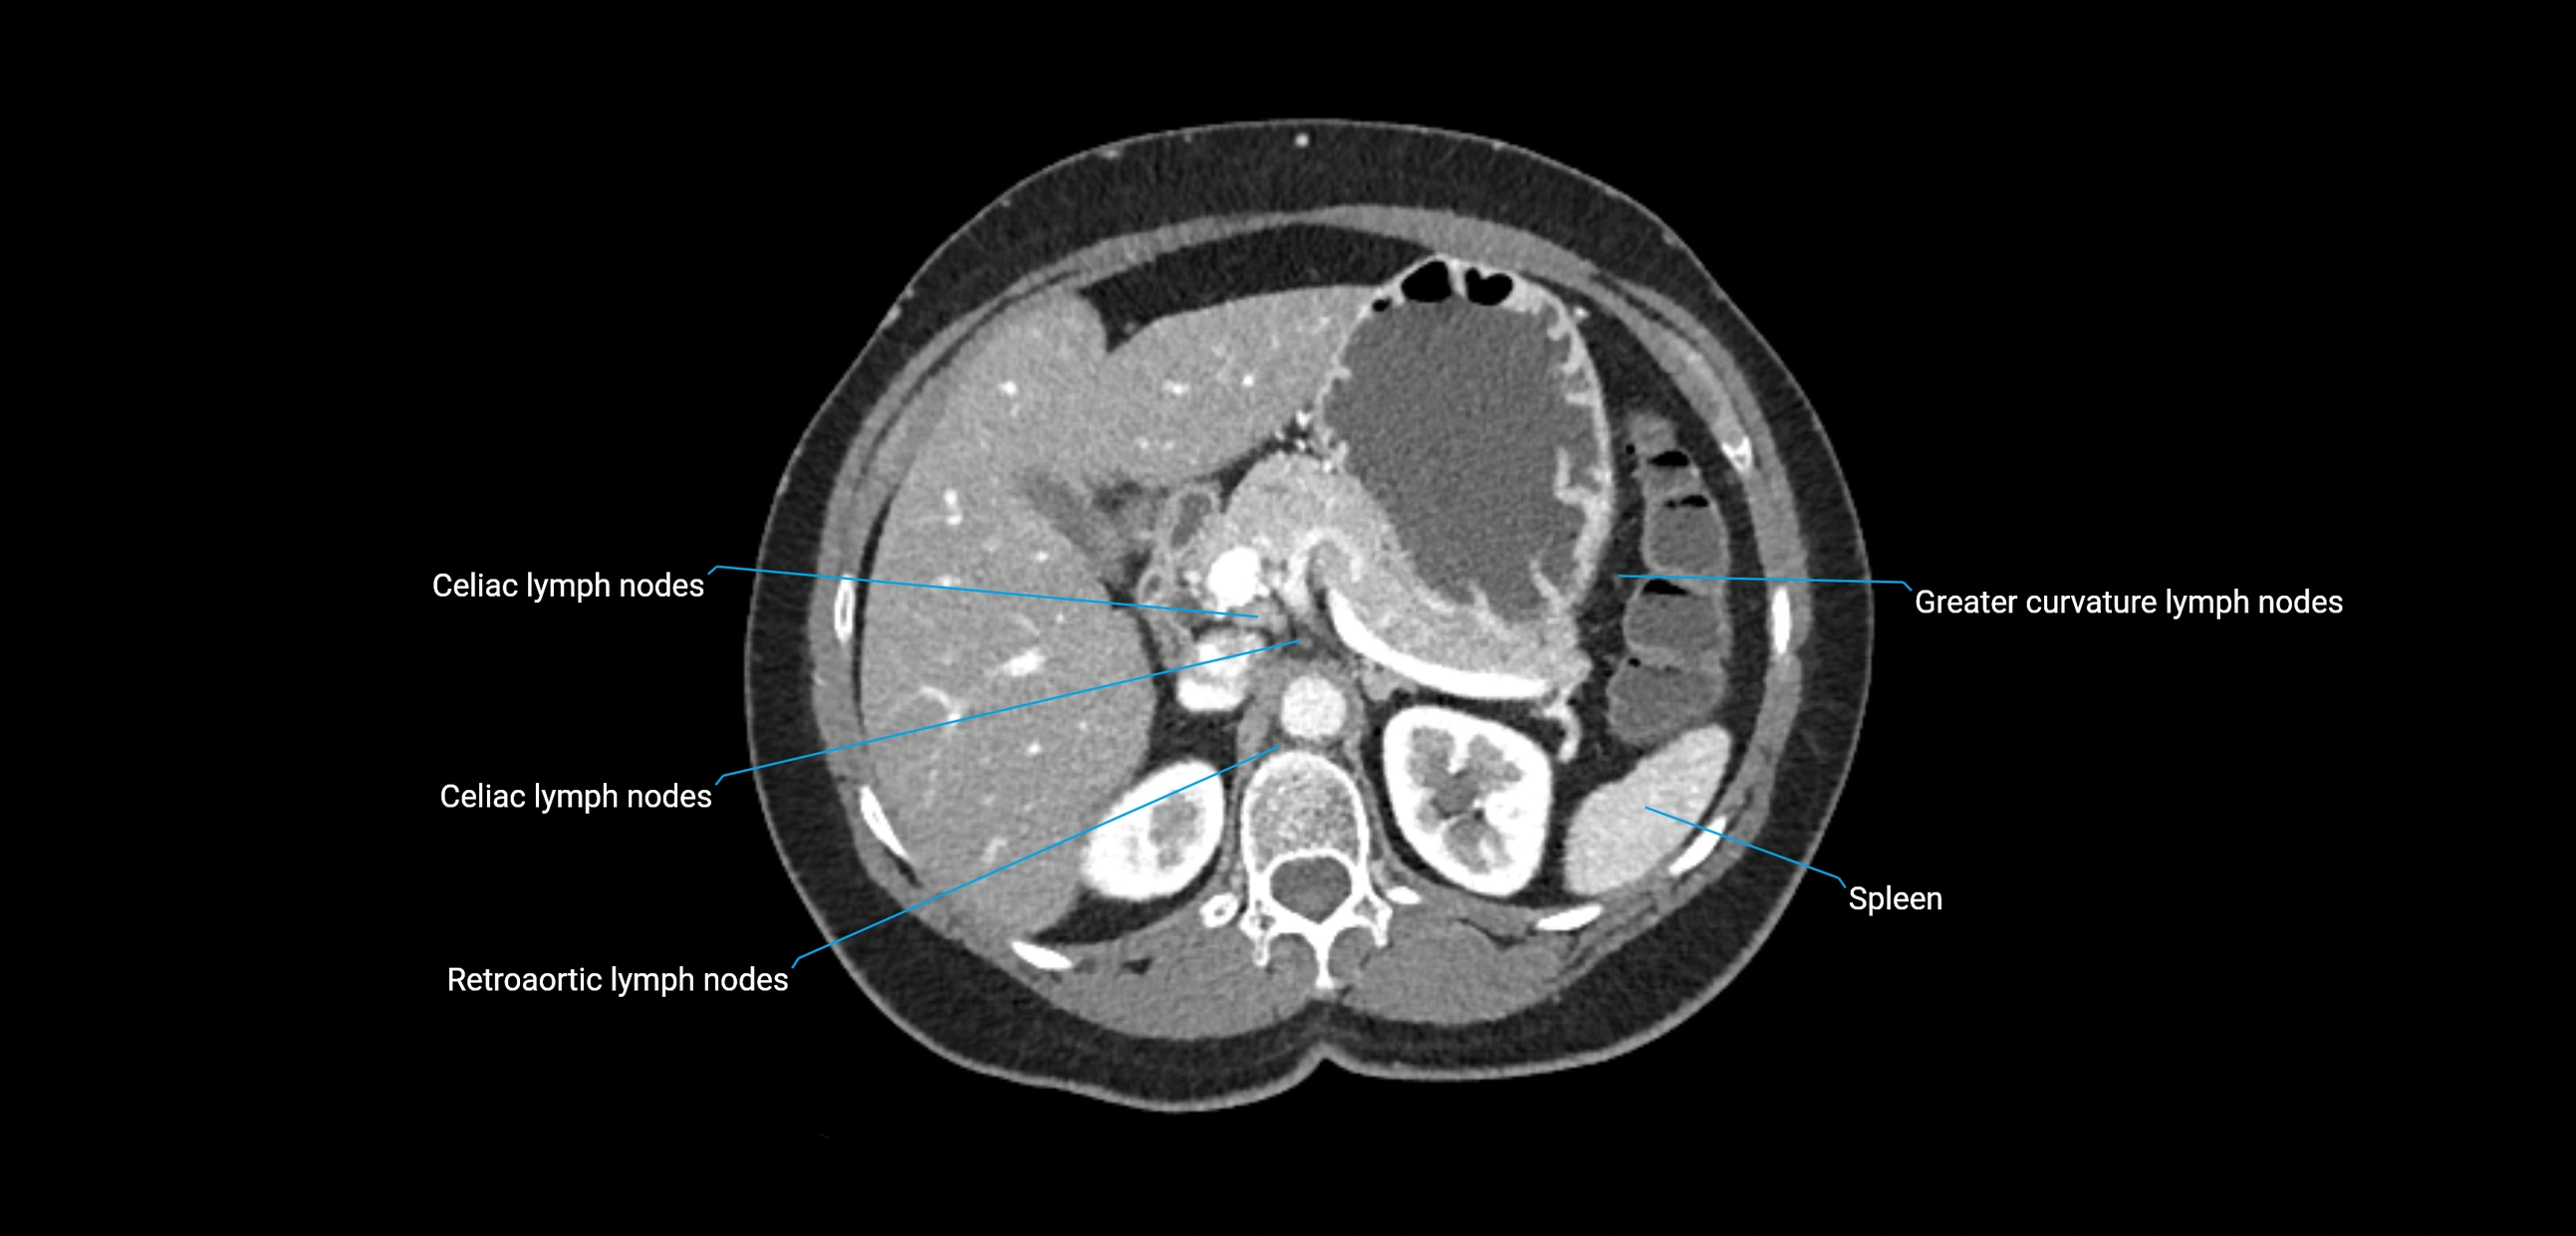

CT image

image